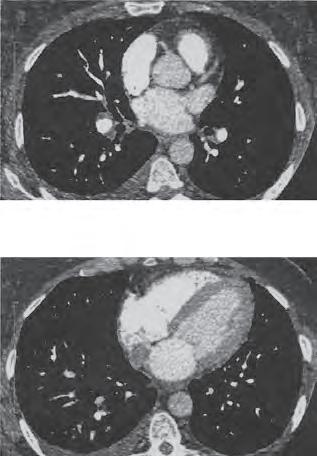

Anatomia per sezioni (continuazione)

Piano di sezione trasversale a livello della 7a vertebra toracica (T7) (A)

Il piano di sezione interessa l’aorta ad altezza delle valvole semilunari (A1). Anteriormente rispetto all’aorta si riconosce la via di efflusso del ventricolo destro, il cono arterioso (A2). A destra l’aorta risulta circondata dall’auricola (A3) dell’atrio destro. Nel tessuto adiposo sottoepicardico (A4) sul lato sinistro, sono state colte in sezione, in prossimità dell’aorta, l’arteria coronaria sinistra (A5) e l’auricola sinistra (A6). La sezione posteriore del cuore interessa l’atrio sinistro (A7) a livello della regione a parete liscia con lo sbocco delle vv. polmonari (A8) inferiori. Posteriormente rispetto all’atrio sinistro e in stretta prossimità con questo si distingue l’esofago (A9).

A10 Ramo dell’a. polmonare destra

A11 Ramo dell’a. polmonare sinistra

A12 Cavità pericardica

A13 Cartilagine costale

A14 Polmone destro

A15 V. polmonare destra inferiore

A16 V. azygos

A17 Aorta discendente

A18 Polmone sinistro

A19 Bronchiolo lobulare destro

A20 Bronchiolo lobulare sinistro

A31 Dotto toracico

Piano di sezione trasversale a livello della 8a vertebra toracica (T8) (B)

Il piano di sezione coglie tutte e quattro le camere del cuore all’altezza delle vie di afflusso attraverso le valvole atrioventricolari. In base al tipo di rappresentazione, l’apice del cuore (B22), formato dal ventricolo sinistro (B21), è diretto in alto a destra. A causa del diverso spessore del miocardio, il ventricolo destro (B23) è facilmente distinguibile da quello sinistro. Nel tessuto adiposo sottoepicardico (B4) sono state colte le aa. coronarie destra (B24) e sinistra (B5). Nella via di afflusso del ventricolo destro sporge la cuspide anteriore della valvola tricuspide (B25), mentre nella via di afflusso del ventricolo sinistro sporge la cuspide anteriore della valvola bicuspide (B26). Nel ventricolo sinistro si riconosce inoltre il robusto gruppo anteriore di muscoli papillari (B27). Tra i due atri è stato colto il setto interatriale (B28) e tra i due ventricoli il

setto interventricolare (B29). Anche in questa sezione è riconoscibile la stretta contiguità tra atrio sinistro ed esofago (B9). L’aorta discendente (B17) confina a sinistra e posteriormente con l’esofago. La v. azygos (B16) si trova in posizione immediatamente anteriore rispetto al corpo vertebrale.

B10 Ramo dell’a. polmonare destra

B11 Ramo dell’a. polmonare sinistra

B12 Cavità pericardica (seno obliquo)

B14 Polmone destro

B15 V. polmonare destra inferiore

B17 Aorta discendente

B18 Polmone sinistro

B19 Bronchiolo lobulare destro

B20 Bronchiolo lobulare sinistro

B30 Atrio destro

B31 Dotto toracico

Indicazioni cliniche Grazie alla vicinanza topografica di esofago e atrio sinistro, nella valutazione del cuore oltre all’ecocardiografia si ricorre anche a una variante transesofagea (elettrocardiogramma transesofageo o Eco TEE). Quest’ultimo è particolarmente utile per la valutazione di patologie a livello delle valvole cardiache, in caso di difetti dei setti e per la valutazione di trombi atriali.

Figura 21.17D TC corrispondente al piano in B

A Piano di sezione trasversale a livello di T7 B Piano di sezione trasversale a livello di T8 Figura 2.17 Anatomia per sezioni (continuazione)